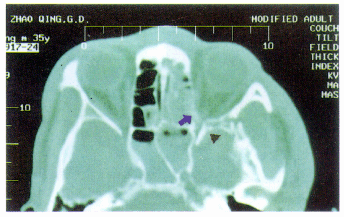

附图 视神经外伤轴位CT。视神经管内侧壁骨折(↑),眶尖部外侧和视神经管外侧骨折(▲)

2. 典型病例介绍:患者男,17岁,摩托车祸致额部撞击伤2天,外伤当时无昏迷,左眼肿胀,未注意视力, 15 h后发现左眼视力差,并呈进行性下降,28 h后左眼失明,仅存光感。外伤后一直用地塞米松、止血剂、抗生素等治疗。检查:左眼光感,Marcus-Gunn瞳孔,左眼球活动正常,玻璃体、眼底均未见异常,右眼视力1.5,视野正常,CT示视神经管内外侧壁骨折,眶外侧壁骨折(附图)。右眼FVEP波形分化好,左眼ERG正常,FVEP显示波形低平不清。外伤后第3天急诊在全麻下行经鼻内窥镜视神经管减压术,术中见后筛窦及蝶窦前壁骨折,窦内陈旧性淤血,左侧纸板后部粉碎性骨折,眶内脂肪溢出,左视神经管内侧壁骨折,蝶窦顶外侧壁视神经管上方交界处脑脊液鼻漏。清理窦内碎骨片和淤血块,磨薄视神经管内侧壁,小心去除骨片至视神经管全长约1/2周径,边缘用小刮匙刮平,视神经鞘膜肿胀膨出,用镰状刀切开视神经鞘膜和总腱环。冲洗术腔,局部填塞含庆大霉素和地塞米松的明胶海绵,外置小块凡士林纱条。术后用抗生素、地塞米松30 mg/d,1h清醒后即发现手动/30 cm,术后第二天视力1m指数,术后11d出院,视力0.25。18 d后复查FVEP出现N、P波峰,但与正常相比较,潜伏期延长和波峰稍减小。术后6个月左眼视力0.4。